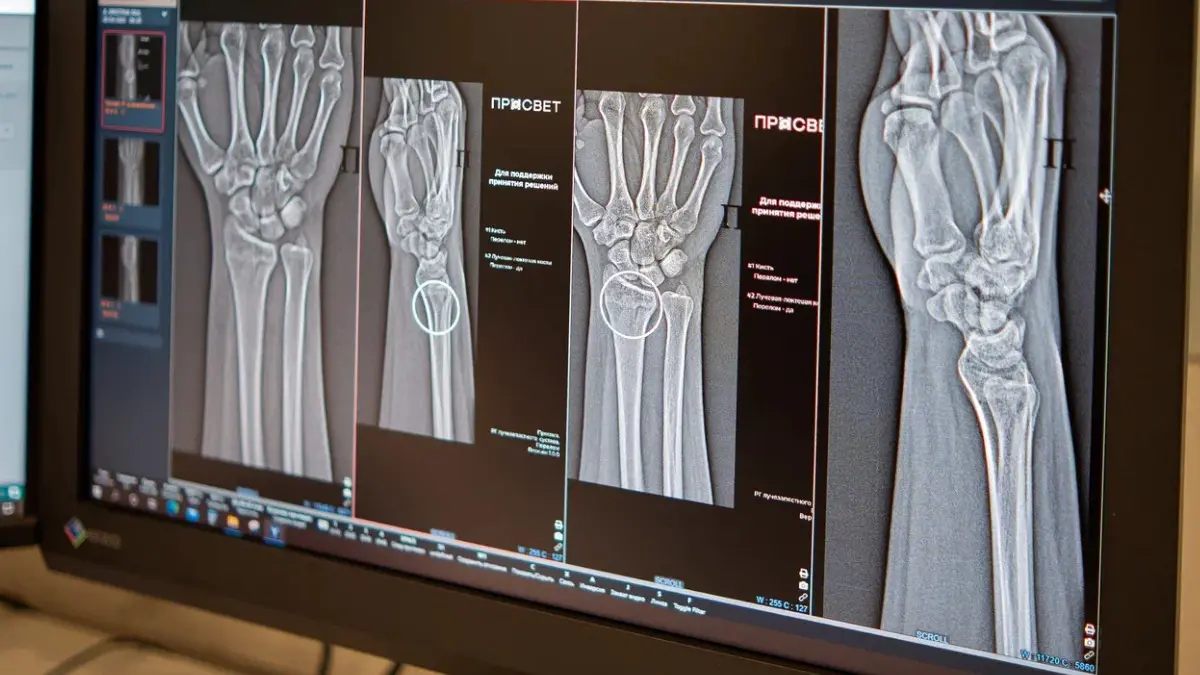

Анастасия Ракова подчеркнула: «Цифровые алгоритмы уже пять лет помогают московским диагностам, главным образом в изучении снимков. Наши новые ИИ-сервисы способны выявлять на рентгене повреждения костей голеностопного и лучезапястного суставов — крайне важных и уязвимых зон. Системы автоматически маркируют травмированные участки и проводят все замеры, даже при нескольких переломах на одном изображении».

Технологии ИИ в радиологии анализируют снимки по множеству характеристик, проводят автоматические расчеты и ускоряют подготовку описаний. Они обнаруживают мельчайшие трещины и предупреждают врача о множественных повреждениях в одной зоне. Точное выявление травмы напрямую определяет стратегию эффективного лечения.